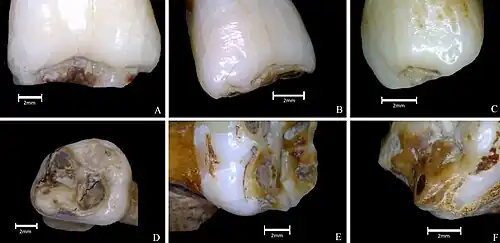

Plane-form enamel hypoplasia

Plane-form enamel hypoplasia is often seen as the most severe type of enamel hypoplasia, and results from enamel matrix formation stopping, resulting in areas of crown with little or no dental enamel deposition.[1][2] With plane form meaning the surface is smooth and flat. A relatively short period of severe stress can potentially lead to a very large defect. Plane-form enamel hypoplasia can be caused by a variety of factors, including severe illness/malnutrition, as well as specific conditions such as amelogenesis imperfecta and congenital syphilis. In severe cases enamel can be completely missing from areas of the crown, exposing the underlying dentine.[1] This condition has been recorded in history since at least the 18th and 19th century. A study was done on a 15-year-old female that was alive during the 18th and 19th century, and she presented enamel hypoplasia.[3]

Signs of plane-form enamel hypoplasia can be observed through pitting, depressions, and grooves seen on the surface of the teeth. This disease can solely affects a person's teeth, causing the enamel on one's teeth to erode. Common signs include white spotting and yellow or orange discoloration on the tooth surface. Patients with this condition often experience weakened and sensitive teeth. Progressive eroding of the enamel causes the teeth to become more sensitive, leading to discomfort when eating or drinking.[4]